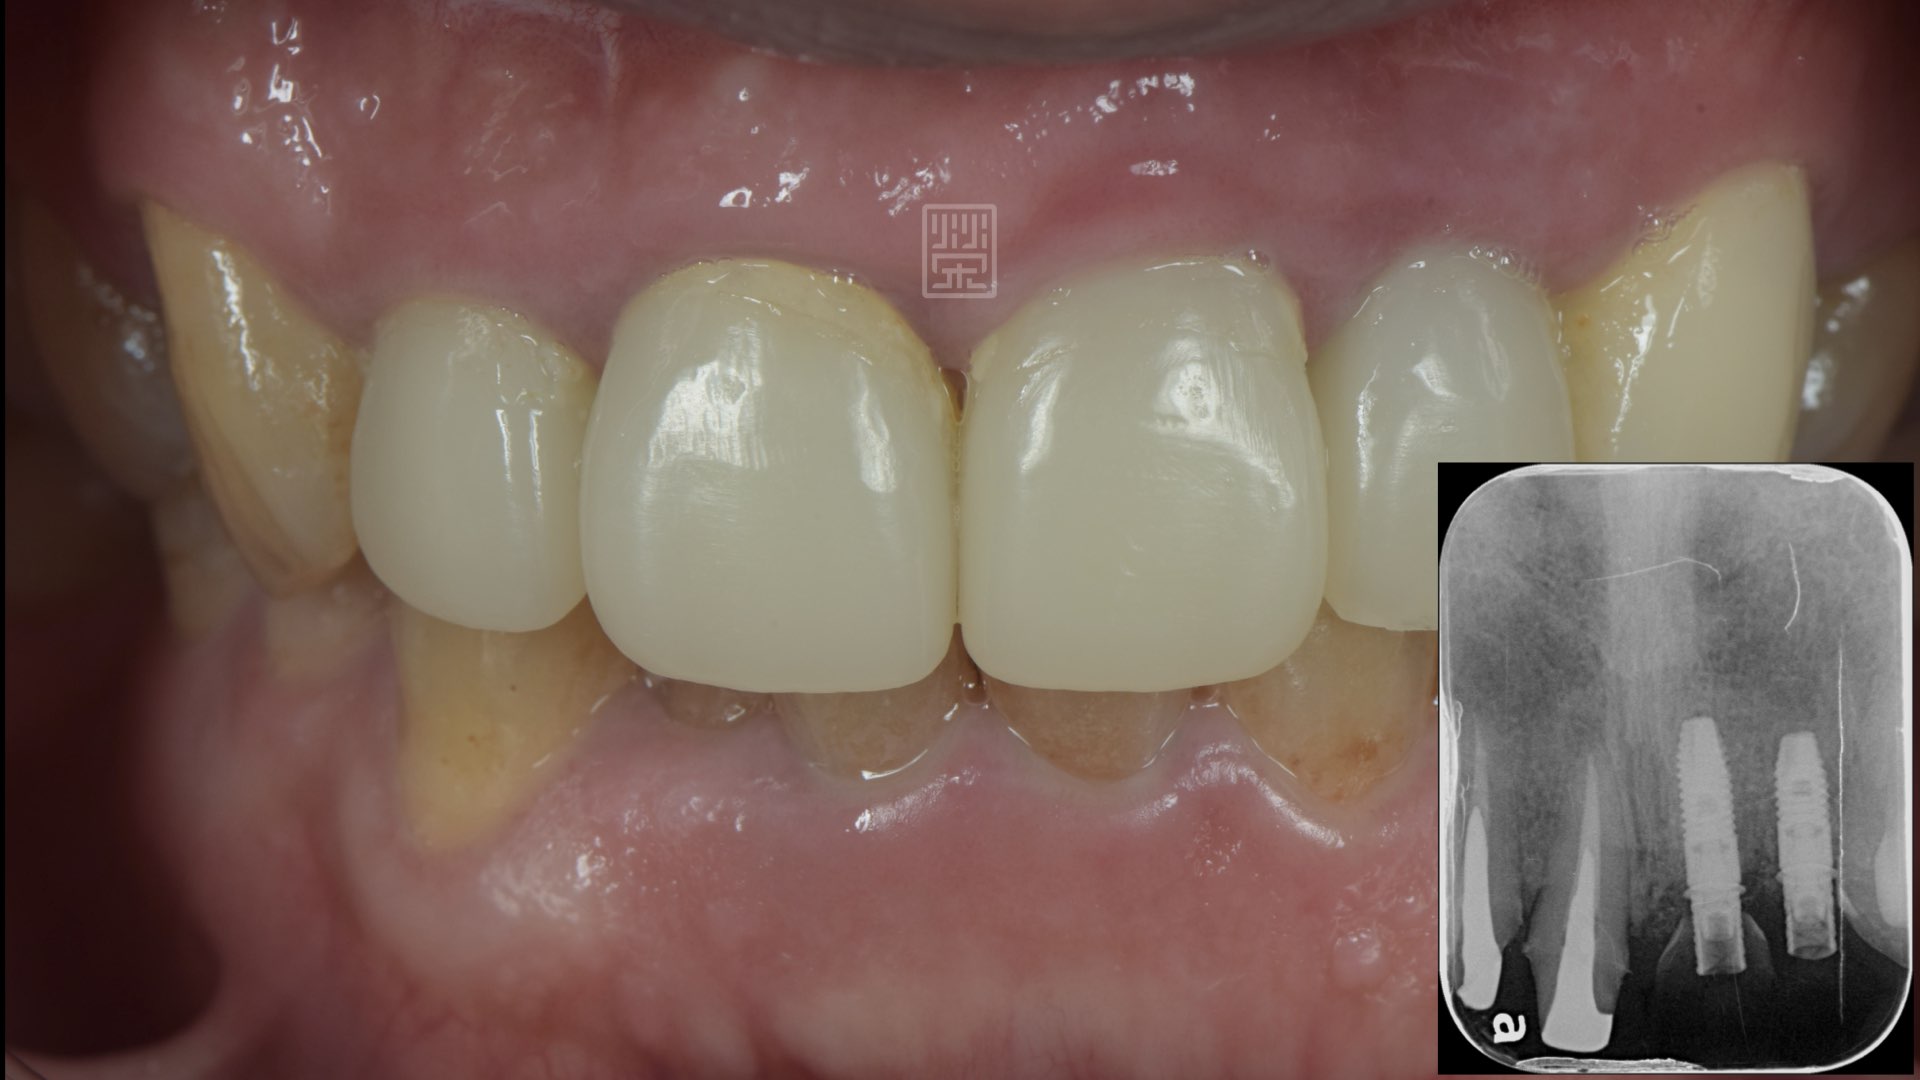

擬真牙齒完成

左側運動與右側運動皆有犬齒導引保護